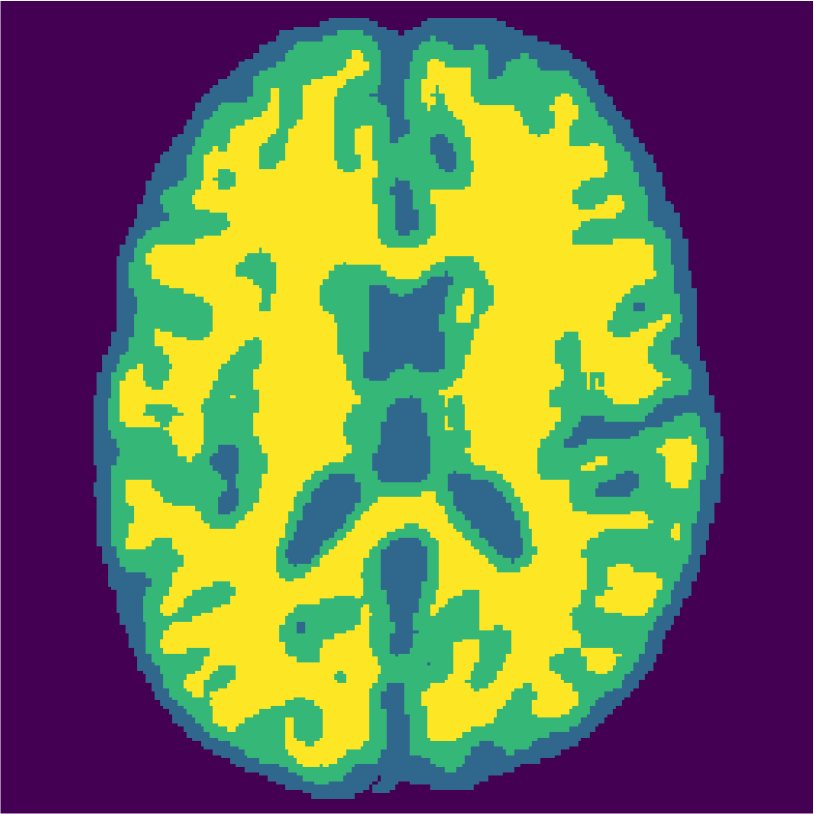

Examples of the segmentation results on one of the target test images are shown in Figure 8 for experiment 2.1, Figure 9 for experiment 2.2, and Figure 10 for experiment 2.3. Examples are shown after using 1 target patch per tissue for training, and after using 100 target patches per tissue for training. The results show that only the mrai-net classifier is able to predict a segmentation that approaches the ground truth with only 1 target patch per tissue for training (error for experiment 2.1 = 0.269, experiment 2.2 = 0.403, experiment 2.3 = 0.320), while the source and target classifiers cannot (source error for experiment 2.1 = 0.667, experiment 2.2 = 0.653, experiment 2.3 = 0.435; target error for experiment 2.1: 0.591, experiment 2.2: 0.614, experiment 2.3 = 0.596). After using 100 patches the source and target classifiers can predict a gross segmentation of WM, GM and CSF (source error for experiment 2.1 = 0.213, experiment 2.2 = 0.384, experiment 2.3 = 0.363; target error for experiment 2.1: 0.205, experiment 2.2: 0.368, experiment 2.3 = 0.368), but the mrai-net classifier prediction shows more details and a lower tissue classification error (error for experiment 2.1 = 0.111, experiment 2.2 = 0.276, experiment 2.3 = 0.284).

2.2) Experiment on 1.5T simulated data and 3.0T real data (Source: Brainweb1.5T, Target: MRBrainS).